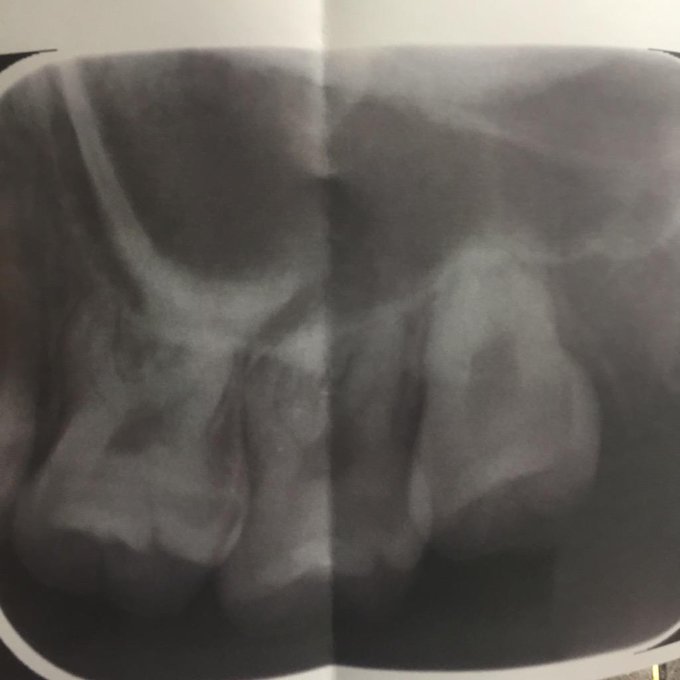

親知らず抜くために歯医者でレントゲン撮ってきたよ!

けど色々な理由が重なって数ヶ月様子を見ることに!!

どちらにしても抜くんだけど、今じゃないことに少しホッとしてる😂

#なっちゃんの親知らず

#レントゲン pic.twitter.com/J0xfIYgMdE